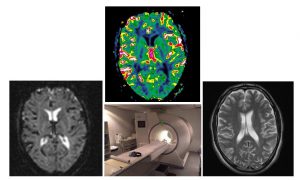

Panou Theodora, Principal Investigator of the researc project entitled: «Cognitive, psychoemotional and neuroimaging predictors of disease progression in the early stages of Multiple Sclerosis»

The objective of the proposed longitudinal study is to investigate cognitive, psychoemotional and neuroimaging parameters, recorded during the early stages of Multiple Sclerosis (MS) that affect long-term disease outcomes. The study capitalizes on comprehensive neuroimaging, neurological, and neuropsychiatric data available on a cohort of 80 patients, who had been recently diagnosed with mild MS in the 2013-4 period, and proposes a comprehensive follow-up neurological and neuropsychiatric evaluation of the same patients using identical procedures after a period of 5 years (i.e., during 2018-9).